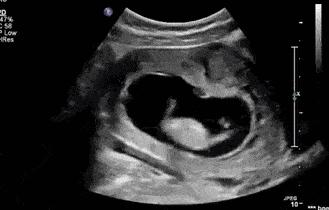

吓得她立刻喊上老公去了医院,以为孩子就要出生了,但是产检医生一看,告诉她,孩子还没有入盆。医生的话犹如冷水一般,刘珊珊坚决不信自己的宝宝还没有入盆,因为她感觉孩子就要出来了一样,带着疑惑检查了B超。

结果显示她的宝宝的确还没有入盆,对此刘珊珊担忧不已,给医生述说自己的症状,医生告诉她,孕晚期胎动频繁很常见,孕妇也会出现各种各样的不适,但是不要慌,宝宝要出来首先要经历的就是入盆,而她的宝宝还未入盆,再者是她没有出现意味着卸货征兆的胎动。